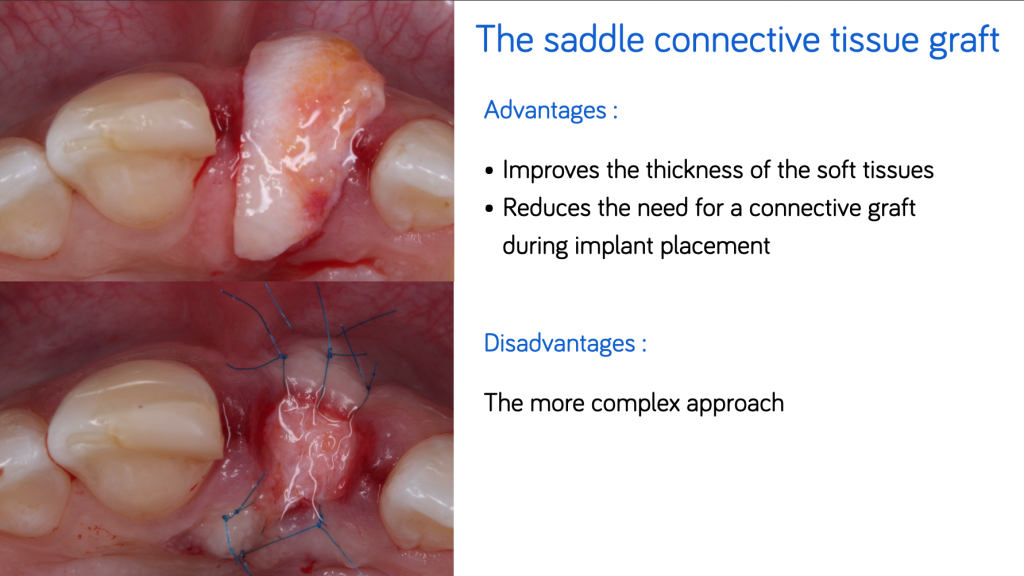

#4. The saddle connective tissue graft

The saddle connective tissue graft associates closure of the extraction site with an increased volume of soft tissues in the buccal part (Chen and Dahlin, 1996).

The graft is positioned in the vestibular and palatal which involves the realization of a buccal supra-periosteal envelope (about 5mm) and a palatal detachment (about 3mm) to introduce the connective graft while preserving the papilla (Fig.5).

The increase in the thickness of the buccal gingiva makes it possible to compensate for the irreversible loss of bone volume despite the filling, and thus to obtain the best horizontal and vertical preservation of the soft tissues (Vanhoutte et al., 2014).

This approach, which is more complex, increases the quantity of soft tissues, particularly in the case of a fine periodontal phenotype, and thus reduces the need for a connective graft during implant placement. Some authors recommend keeping an epithelial area on the exposed part of the graft.